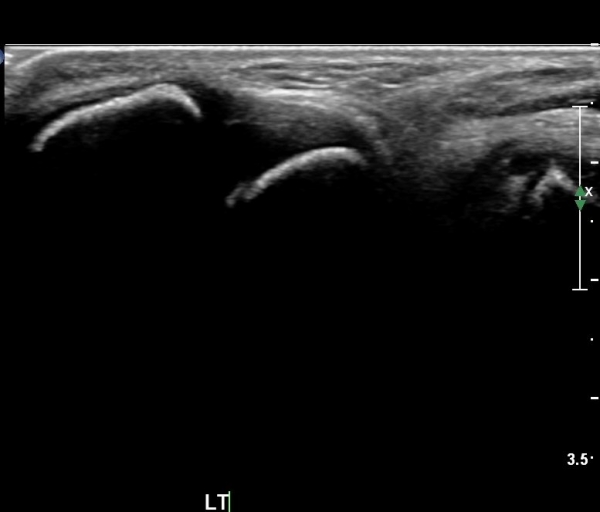

Àü°ÅºñÀÎ´ë ºÎÀ§ ±¹¼ÒÀû ¾ÐÅë, ºÎÁ¾À» º¸ÀÓ. Àü¹æ´ç±è°Ë»ç (+)

ÃÊÀ½ÆÄ °Ë»ç